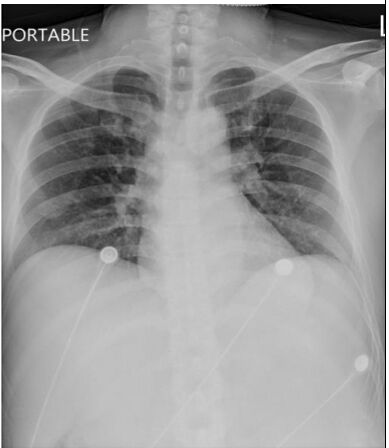

4. 病人是位29歲男性電子工程師派駐中國深圳,三個星期來,時有間歇性發燒及逐漸性呼吸困難,先在深圳 門診求醫,初以為一般感冒治療,後以支氣管炎診斷治療罔效,乃急回台灣求醫。經檢查,意識: E4M6V5; BP: 122/75 mmHg; PR: 116/min; RR: 21/min; Temperature: 37.6℃; SPO2: 94%(room air) 頸靜脈不怒張,未有貧血,胸部呈現瀰漫性濁音,心臟擴大,有Grade III/VI Diastolic murmurs at left upper sternal border,無肝脾腫大,無腹水。皮膚未有紅腫或出血斑點。2016/12/23心電圖及胸部X光如 圖。其血液、尿液及生化如次:Hemograms: WBC, 13.54(k/uL); RBC, 4.74(M/uL); Hb, 13.0 (gm%); HCT,40.2(%); MCV, 84.8 (fL); MCH,27.4(pg); Platelet,329 (k/uL); Seg, 81.5(%); Eos, 0.2(%)。尿檢: 正常。請 問這位年青病人的最可能診斷是:

(A) Acute heart failure with lungs infection。 (B) Acute pericarditis。 (C) Acute viral myocarditis。 (D) Acute infective endocarditis。 (E) Acute pulmonary thromboembolism。